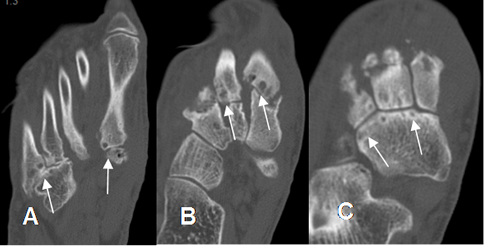

Fig 130 A. Artropatía degenerativa.

A: Rx lateral, B: TAC reconstrucción sagital y C: RM sagital en T2. Presencia de cambios degenerativos, con formación de osteofitos en la articulación taloescafoidea.

Fig 130 B. Artropatía degenerativa.

A, B y C: TAC axial. Cambios degenerativos con disminución del espacio y lesiones osteocondrales, en las articulaciones de Lisfranc (A y B) y de Chopart. (C).